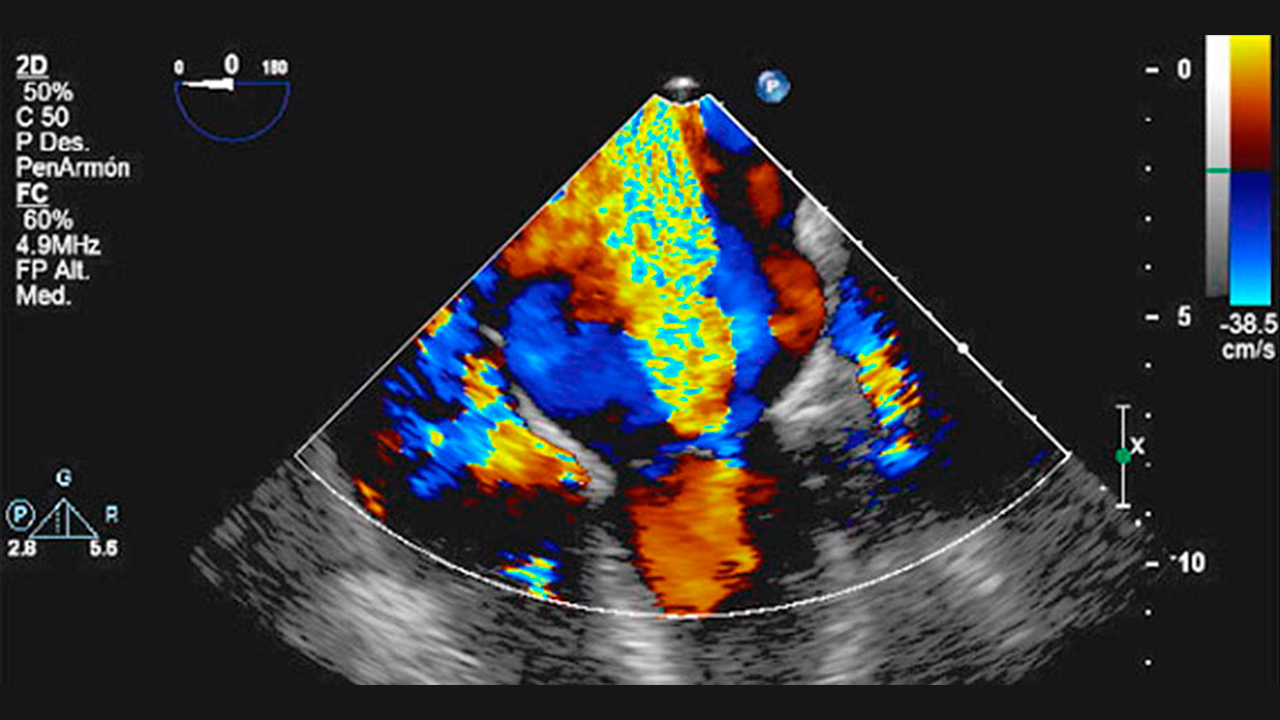

Ecocardiograma Transtorácico y Transesofágico

El ecocardiograma transtorácico no provoca molestias y no necesita preparación, consiste en la colocación externa del transductor en la pared torácica para ir observando las diferentes partes del corazón. La ecocardiografía transesofágica se realiza con una sonda a través de la boca y requiere sedación.